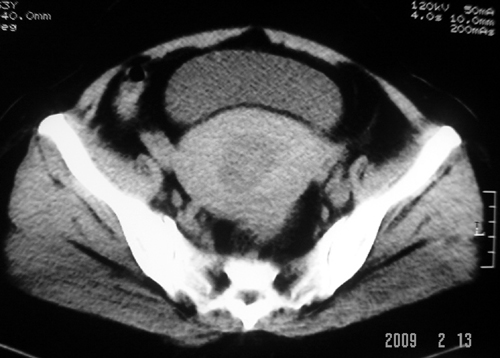

以下是引用余辉在2009-2-14 8:37:00的发言:[br]宫颈左后壁见较大低密度肿物影且向左后上方突出,宫腔内见大片状低密度区,考虑宫颈肿瘤,宫颈癌可能性大,伴宫腔积液或转移